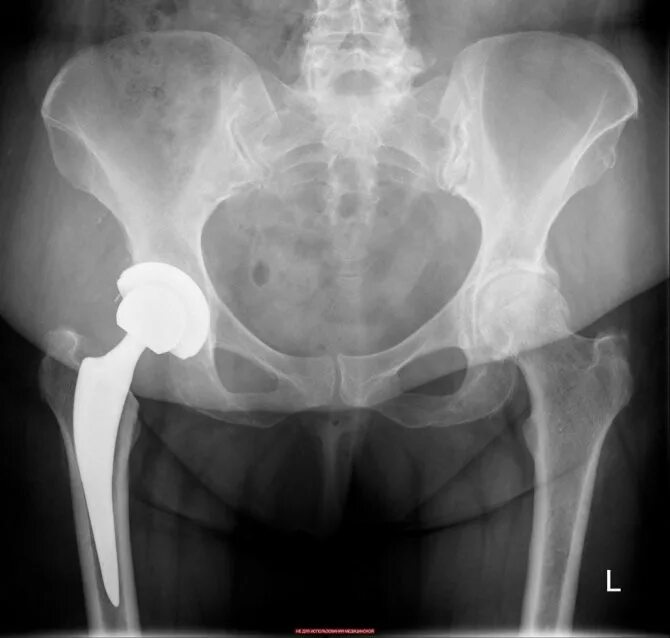

Эндопротезирование тазобедренного сустава видео